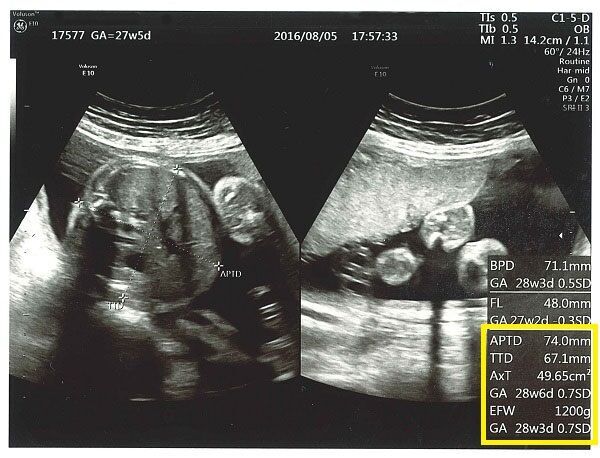

超音波検査装置は、超音波検査装置または超音波検査から得られる画像です。乳児超音波検査は、胎児の成長を画像化したもので、医師やその他の専門家が妊娠の健康状態をチェックし、即時の治療が必要な基礎的な健康状態を特定するのに役立ちます。

超音波検査は、超音波が組織で反射したときに作成される画像です。超音波検査装置は、超音波検査者が超音波検査図を生成するために使用する装置です。胎児超音波検査または出生前超音波検査は、胎児の超音波検査の別名です。

スキャンの目的に応じて、超音波技師が画面上の画像を測定する場合があります。